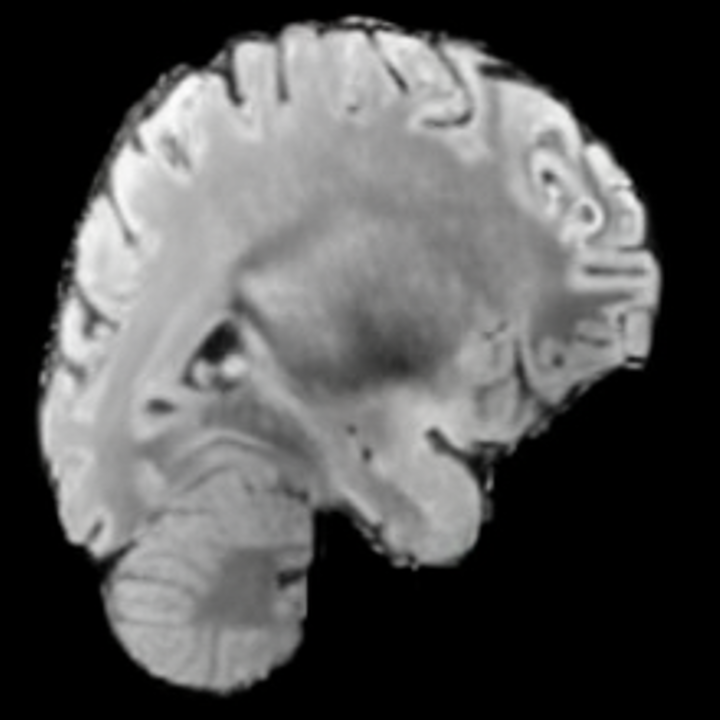

Preservation of Spine Curvature. For the spine segmentation on UK Biobank, we use a UNet++ model [81] with Dice Loss and use the curvature prediction of the spine followed in [9]). We measure the Pearson correlation factor [9] of spine curvature measured on the generated MRIs where the input is a single MRI coronal slice, or a single sagittal slice against the curvature of reference real MRIs of the same samples. The correlation coefficients are 0.89 for the coronal MRIs and 0.88 for the sagittal MRIs on the test set of 308 human-annotated angles.

B.3 Preservation of Spine Curvature and Fat

For the spine segmentation on UK Biobank, we use a UNet++ model [81] with Dice Loss. We use a model trained to predict curves on DXA on UK Biobank [9]. We show in Figure 20 that generated MRIs preserve the spine curvature from normal to severe scoliosis cases. We also study the case when DXA is used to generate the MRIs and show in Figure 14 how the correlation to real curvatures compares to the input MRI case. The curvatures of the MRI generated from the coronal plane match the DXA curvatures more than the curvatures generated from sagittal MRI. This is expected since the antero-posterior plane of DXA is equivalent to the coronal plane for MRIs. This also explains the greater Pearson’s correlation coefficient of the coronal MRI (0.89) and DXA-generated curvature (0.88) compared to sagittal-generated curvature (0.87) relative to the reference curvature on the coronal plane. We observe though that MRI generation using X-Diffusion from another plane than the conventional plane for scoliosis assessment is valid.